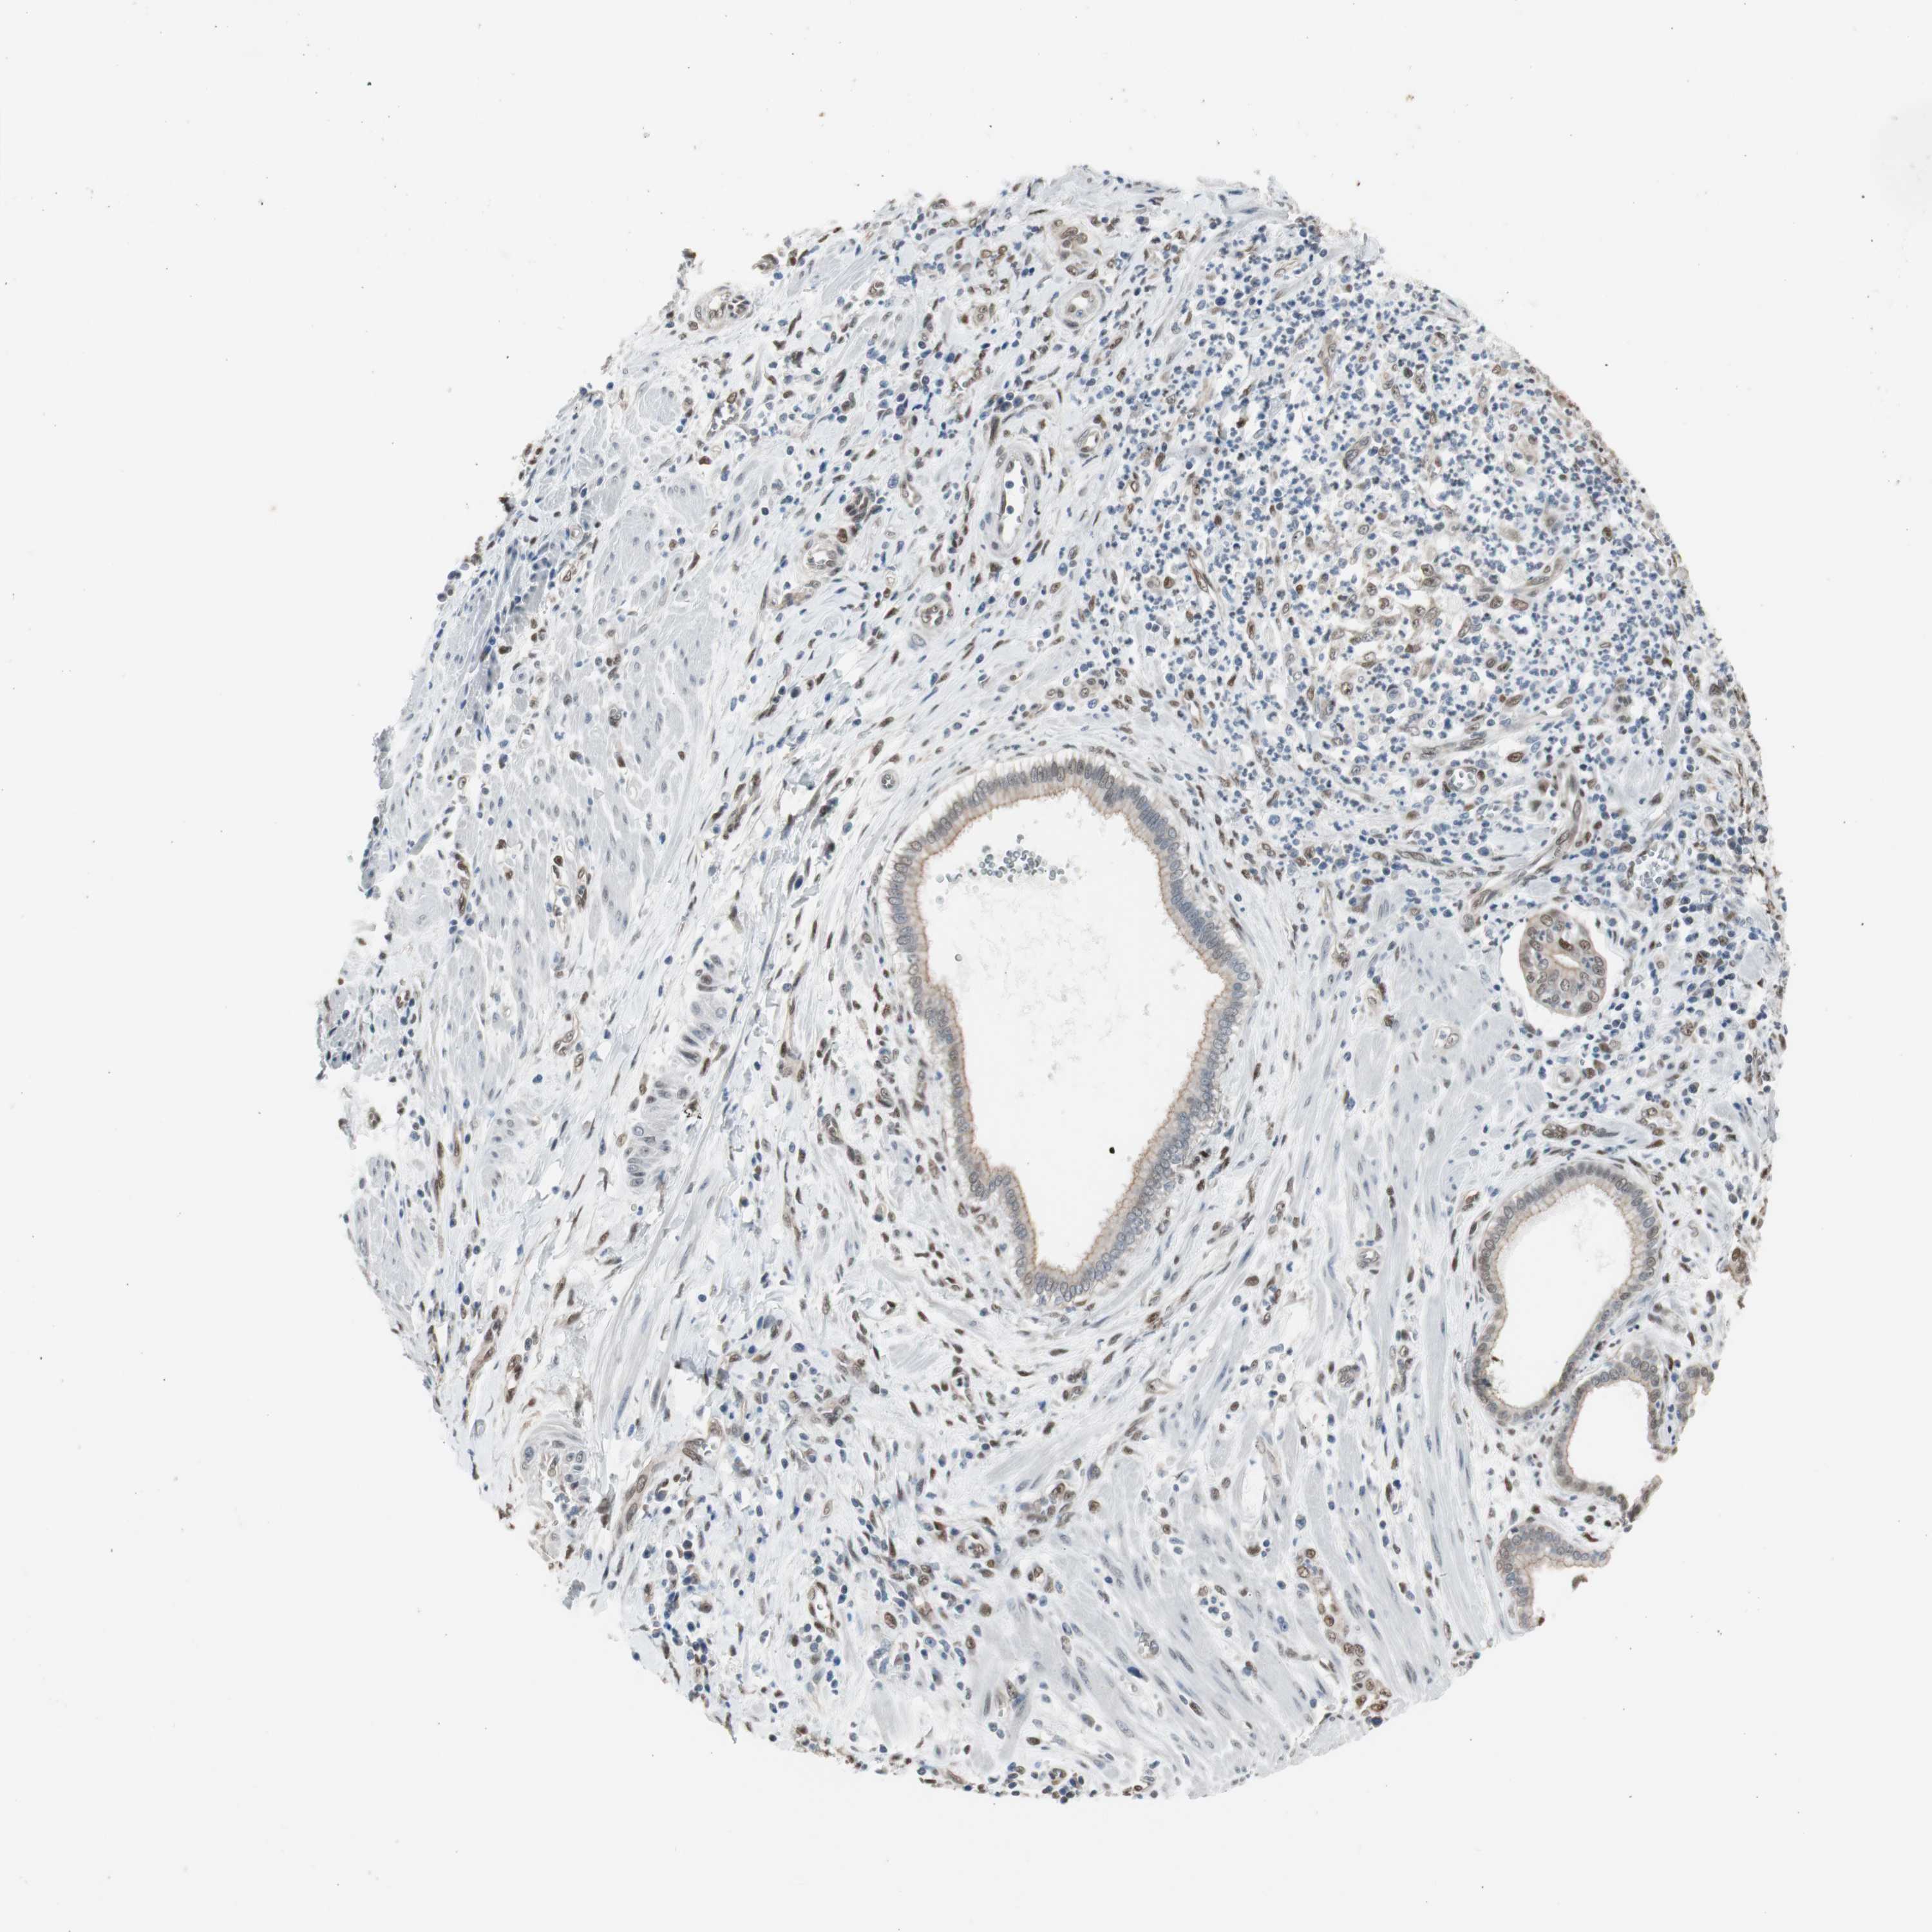

PANCREATIC CANCER - Protein expressioni

A mouse-over function shows sample information and annotation data. Click on an image to view it in a full screen mode. Samples can be filtered based on level of antibody staining by selecting one or several of the following categories: high, medium, low and not detected. The assay and annotation is described here.

Note that samples used for immunohistochemistry by the Human Protein Atlas do not correspond to samples in the TCGA dataset.

Antibody stainingi

Antibody staining in the annotated cell types in the current human tissue is reported as not detected, low, medium, or high, based on conventional immunohistochemistry profiling in selected tissues. This score is based on the combination of the staining intensity and fraction of stained cells.

Each image is clickable and will lead to virtual microscopy that enables deeper exploration of all samples and also displays staining intensity scores, fraction scores and subcellular localization as well as patient and tissue information for each sample.

Antibody HPA008312

Antibody CAB010194

Antibody CAB016304

Staining

High

Medium

Low

Not detected

Intensity

Strong

Moderate

Weak

Negative

Quantity

>75%

75%-25%

<25%

None

Location

Nuclear

Cytoplasmic/membranous

Cytoplasmic/membranous,nuclear

Adenocarcinoma, NOS

Adenocarcinoma, metastatic, NOS